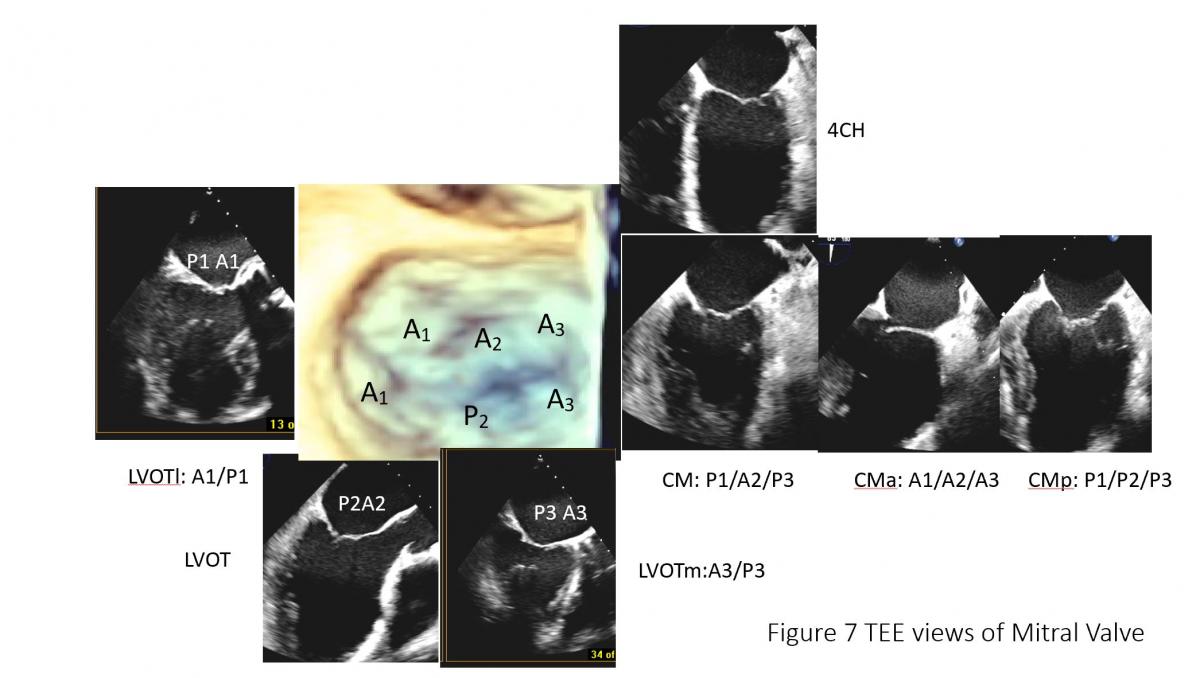

Figure 6: Illustration of TEE probe with its steerability and ability to image different components of mitral leaflet structures. A: Steerability of the TEE probe, sector angle rotation from 0o to 180o, probe rotation, anterior flex (anteflex) and posterior flex (retroflex) of the probe and medial (left) and lateral (right) flex of the probe), potential views of TEE in the mid esophageal position with manipulation of steerable TEE probe. Ao: Aortic valve/aorta, LAA: left atrial appendage, 4CH: 4-chamber view of mid esophageal TEE probe position with probe sector rotation at 0-10 degree, CM: commissure view of mitral valve with 50-70 degree of sector angle rotation, with anteflex and retroflex of the probe from CM view, CMa and MCp can be obtained (C). CMa: anterior to CM view (Figure C lower, MCp: posterior to CM view (Figure C, lower), 2CH: 2-chamber view with TEE probe sector rotation of 80-100 degree, LVOT view or LV long-axis view with sector angle rotation of 120-150, LVOTm: medial to LVOT view with probe medial rotation or flex with or advancing the probe, LVOTl with probe lateral rotation or flex or pulling back of the probe (Figure C, upper). Posterior mitral leaflet is segmented into P1, P2 and P3 from the aorta/LAA anterolateral to inferomedial direction, Similarly, anterior leaflet is divided into A1, A2, A3 accordingly. Note: anatomic separation is present for posterior leaflet and no anatomic marker to separate A1 to A2 or A2 to A3.

Figure 7: TEE of mitral valve: mitral leaflet segments on common of TEE views. CM: Commissural view of mitral valve (60 degree), CMa: anterior rotation to obtain CMa with A1A2A3, posterior rotation (CMp) to obtain P1P2P3, LVOT view with A2 and P2 and LVOT lateral maneuvering to get LVOTl with A1and P1 and LVOTmedial maneuvering to get P3 and A3 segment of mitral leaflets.

Selection of anatomically and mechanistically suitable patients for MitraClip will largely determine procedural success and short-term outcomes. Currently anatomy and mechanism of mitral regurgitation is primarily evaluated by detailed TEE assessment of mitral valve (Figures 6-7). Cardiac CT (Figure 8) can be used when there is requirement for better assess leaflet calcification if TEE is uncertain. It is important to have standard imaging protocol and terminology for communication between TEE imager and implanter prior, during and post clip for procedural efficiency, procedural success and outcome of the intervention.

To facilitate the communication, both echocardiographer and implanter should be familiar with essential TEE imaging views during mitral clips (Figures 6-8). For transseptal guidance, bicaval TEE view and short-axis basal heart (aortic valve) view are commonly used and often in a XPlane/biplane view (Figure 9). For device advancement guidance in the LA to mitral valve oblique 45 degree view of left pulmonary vein, left atrial appendage/coumardin ridge is often used (Figure 9). For mitral valve, 4-chamber (Figure 7), commissure 2-chamber view (Figures 7-8), LVOT long-axis or 3-chamber view (Figures 7-8) are most commonly used. Off axis 2-chamber views (Figures 7-8) and off-axis LVOT views (Figures 7-8) are used to see P1/A1 and P3/A3 segments of mitral valve. 3D TEE of en face mitral valve view with and without color Doppler flow mapping (Figure 10) is used to guide positioning clip system and clip arm alignment.